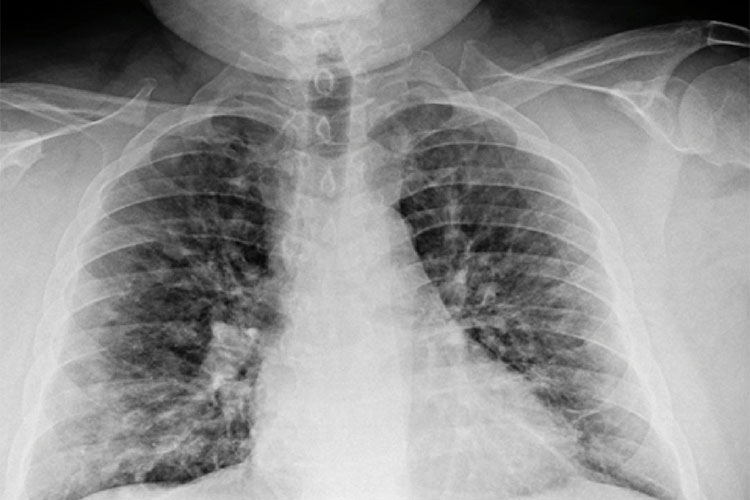

本数据集包含7278张X光胸片图像,并附带YOLO格式的标注,旨在通过YOLO模型进行肺炎及结核病的自动化检测。数据集中共包括四类标签:0表示健康,1表示肺炎,2表示潜伏性结核病,3表示活动性结核病。每张图像均进行了精确标注,以支持卷积神经网络等深度学习模型的训练和测试。该数据集可用于肺部疾病检测模型的开发与评估,尤其适合针对胸片数据的深度学习研究。